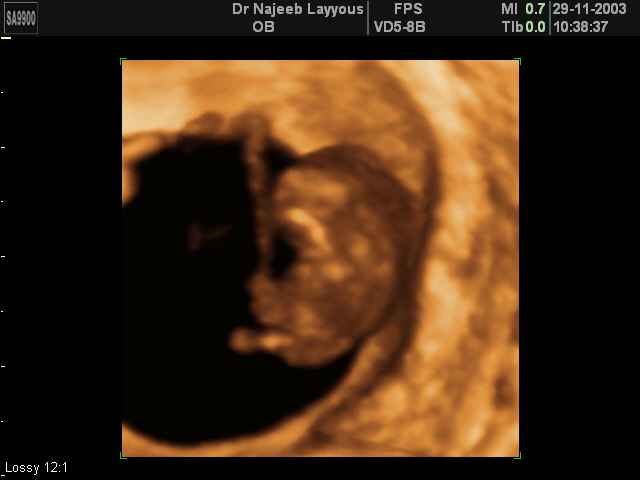

3D First Trimester Ultrasound Scan Photos